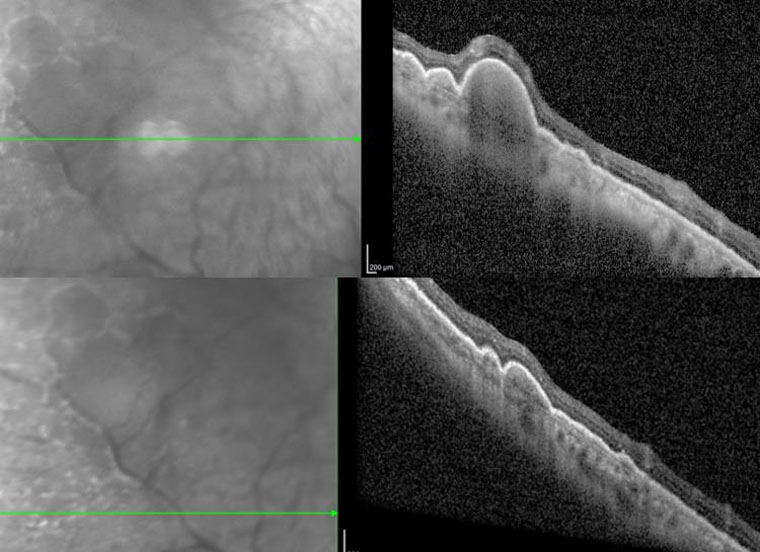

右眼OCT(光学相干断层扫描)

郝玉华主任及其团队仔细翻阅既往病例资料,完善相关眼科检查,根据双眼玻璃体内大量细胞、OCT提示视网膜外层结节样病变和眼底隐约可见黄白色病灶的症状,高度怀疑双眼眼内淋巴瘤合并中枢神经系统受累,经与患者及家属详细交代病情,决定行右眼诊断性玻璃体切除手术以明确诊断。